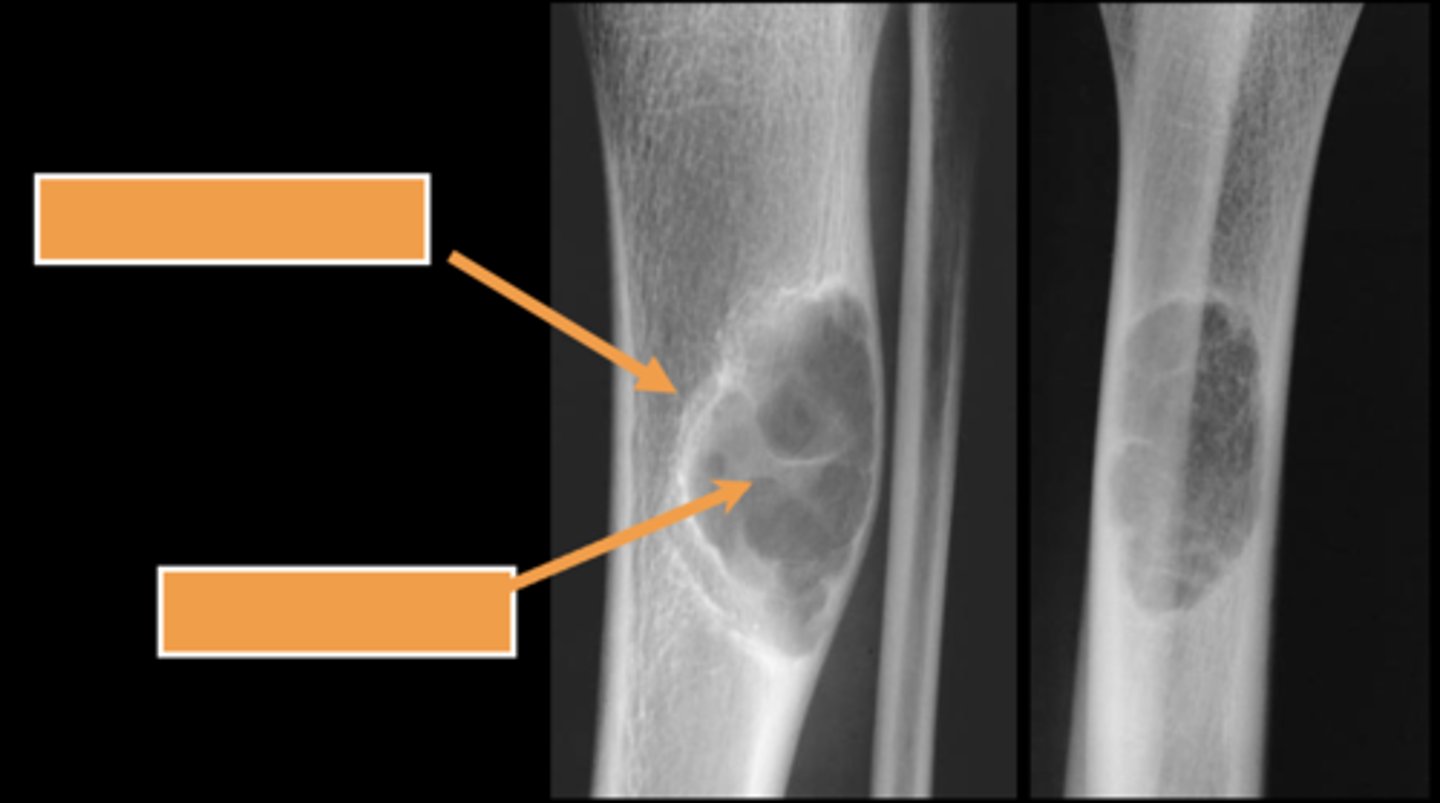

Geographic bone blister

ID radiographic feature of non-ossifying fibroma indicated by top arrow

Septations

ID radiographic feature of non-ossifying fibroma indicated by bottom arrow